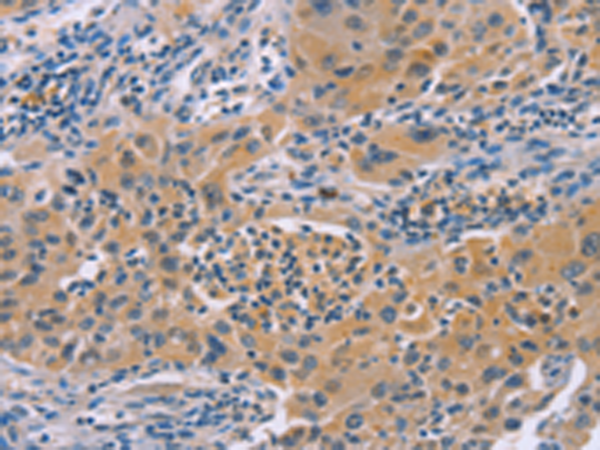

分类: 科研抗体货号: P00470别名:应用: IHC反应种属: Human